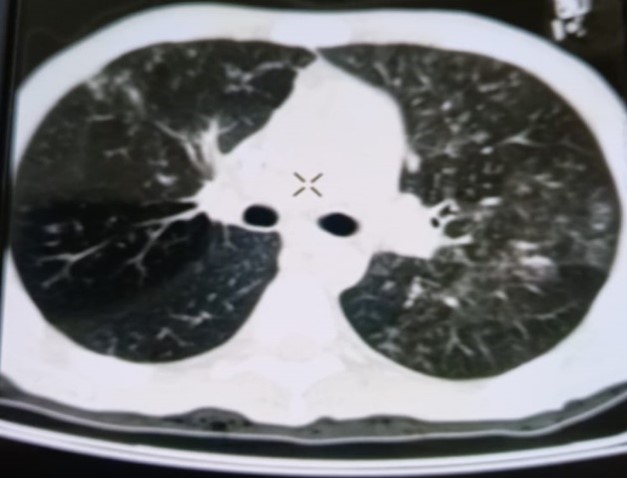

При проведении рентгенологического исследования органов дыхания в динамике спустя 2 недели с момента начала терапии данные компьютерной томографии высокого разрешения указали на следующие изменения: на фоне очаговой диссеминации в легких значительно увеличились по площади участки "матового стекла" в верхних долях обоих легких (описанные зоны неоднородные, сливные); площадь поражения легочной ткани - около 35-40%. В средних и нижних отделах легких с двух сторон выявлялись многочисленные перибронхиальные очаги до 3 мм в диаметре по типу «дерево в почках». В S 6 справа определялась зона альвеолярной инфильтрации. Выпот в плевральных полостях не определялся; внутригрудные лимфоузлы не увеличены. Заключение: признаки двусторонних полисегментарных интерстициально-инфильтративных, диссеминированных мелкоочаговых изменений легких, средняя вероятность вирусной пневмонии (в том числе COVID-19), в сочетании с диссеминированным процессом в легких (рис. 1-4).

Рисунок 1

Рисунок 2

Рисунок 3

Рисунок 4

Рис. 1-4. Компьютерная томограмма пациента Т., с ВИЧ: чередование участков «матового стекла» с диссеминированным процессом, инфильтрацией легочной ткани справа, наличие симптома «дерево в почках» (респираторный бронхиолит).

Учитывая на подозрительные в отношении туберкулеза легких КТ-признаки, пациенту впервые проведена метод ПЦР-диагностики выявления ДНК микобактерий туберкулеза, который показал положительный результат, что позволило установить диагноз «Диссеминированный туберкулез легких, двусторонний. КУМ «-» в сочетании с коронавирусной инфекцией COVID-19 средней степени тяжести, пневмоцистной пневмонией и бактериальной пневмонией» у пациента с ВИЧ-инфекцией 4В стадии. Для дальнейшей терапии пациент был переведен в стационар туберкулезного профиля.